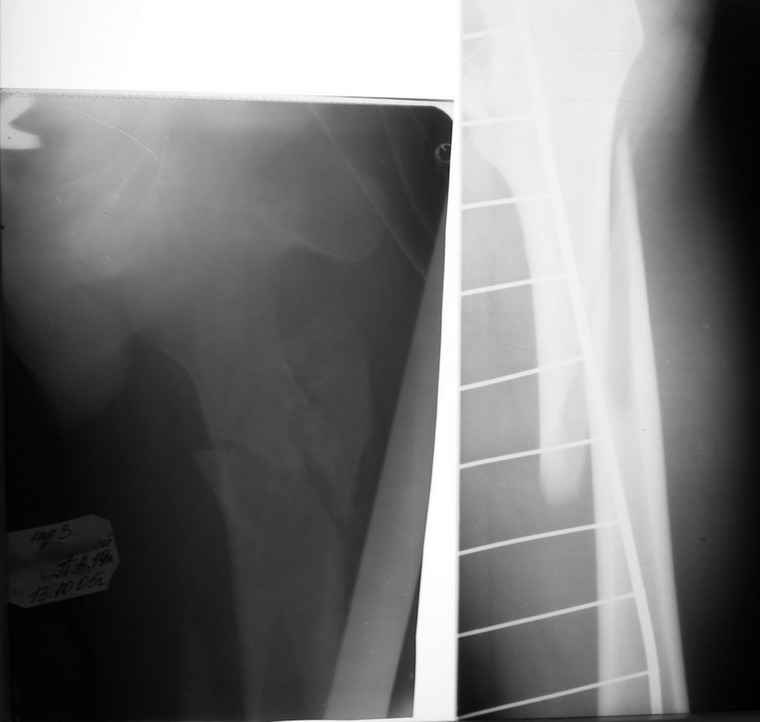

Вот снимки по свежей ситуации, парень 19 лет, длинный оскольчатый перелом бедра от шейки до в-с/3. давно уже ходит на своих ногах.

Представленные Вами рентгенограммы действительно являются примером качественной фиксации спице-стержневым аппаратом. Они, как ни что другое, многое иллюстрируют.

Кроме того, было бы ошибкой ставить знак равенства между нашим и Вашим пациентами. Они не только не похожи, разница между ними просто огромная. Говорю это не для того, чтобы задеть Вас или обидеть. Ни в коем случае. Просто теперь я понимаю, что Ваше мнением строится на простом преломлении Ваших подходов к лечению пациентов со свежими переломами, на ситуацию, абсолютно несопоставимую, подобную нашей.